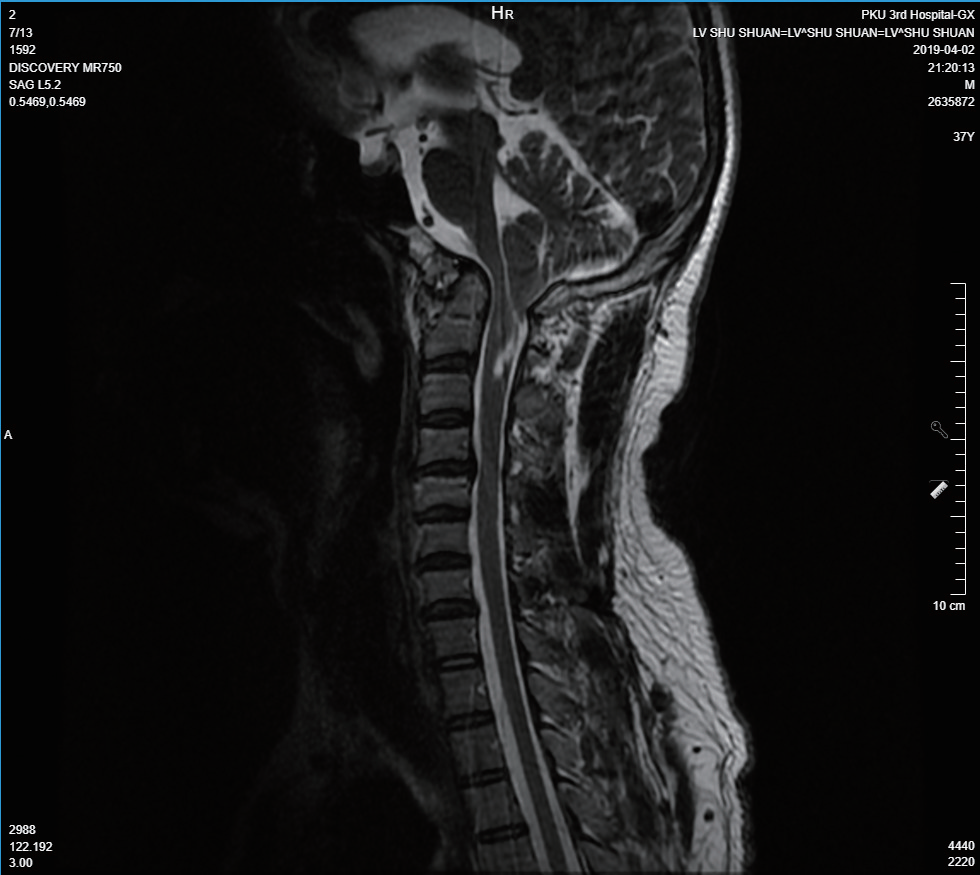

头颅MRI证实Chiari畸形(小脑扁桃体下疝畸形)(图2)。

神经内科意见 查体可见患者存在眼球震颤,左侧肢体温度觉、痛觉减退,咽反射减退,查体双手关节肿胀,结合既往6年前颈椎MRI显示小脑扁桃体下疝,脊髓空洞 ——符合Chiari畸形。考虑为小脑扁桃体下疝压迫延髓呼吸中枢,进而导致患者出现Ⅱ型呼吸衰竭。

神经外科意见 患者既往颈椎MRI示小脑扁桃体下疝,考虑为先天性,可压迫延髓内呼吸和吞咽中枢的功能,导致出现吞咽困难,进食易呛咳,严重时可出现呼吸困难。此患者有进食呛咳,耳鼻喉科会诊检查发现轻度吞咽功能障碍,出现呼吸困难伴有Ⅱ型呼吸衰竭,可用此病解释。建议复查头颈MRI。下一步可手术治疗。

呼吸与危重症医学科 患者睡眠呼吸暂停、肺泡低通气与Chiari畸形有关。Chiari畸形通过压迫延髓呼吸中枢及后续形成的脊髓空洞,致呼吸驱动产生与下传障碍,并影响上气道功能,导致中枢性睡眠呼吸暂停、肺泡低通气和阻塞性睡眠呼吸暂停,长期作用引发肺动脉高压。此次Ⅱ型呼吸衰竭考虑合并呼吸道感染进一步增加呼吸阻力负荷,使肺泡低通气加重所致,严重低氧诱发右心衰与全心衰。

image.png

图2 头颅MRI:小脑扁桃体下疝,符合Chiari畸形。本次复查MRI与6年前未见明显变化。

Chiari畸形又称为小脑扁桃体下疝畸形,其引起睡眠呼吸暂停的机制主要涉及中枢性和周围性双重病理生理改变。该患者小脑扁桃体下疝并发脊髓空洞,致减弱的呼吸驱动下传障碍,导致中枢性睡眠呼吸暂停与肺泡低通气;同时,下疝组织可能累及迷走神经和舌咽神经,引起咽喉肌协调障碍,加重上气道塌陷,促成阻塞性睡眠呼吸暂停。解剖学上,后颅窝容积不足可致周围组织前移,间接压迫上气道,增加睡眠时气道阻力。约50%患者合并脊髓空洞,若累及颈髓(C3-C5节段)可损害膈神经功能,导致呼吸肌无力,进一步加重通气障碍。此外,脑脊液循环受阻引起的颅内压升高可能通过影响呼吸肌的神经支配而抑制通气功能。这些机制共同导致患者出现混合型睡眠呼吸暂停(中枢性与阻塞性并存),并引发慢性肺泡低通气和Ⅱ型呼吸衰竭。治疗包括神经外科干预(如后颅窝减压)和呼吸支持(无创通气)。